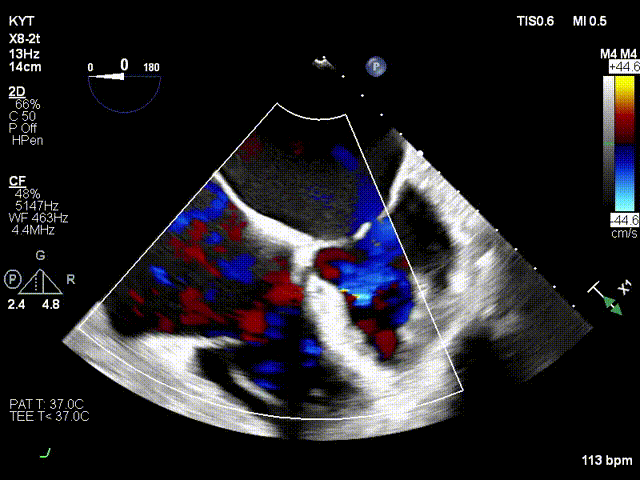

术前超声

术后超声